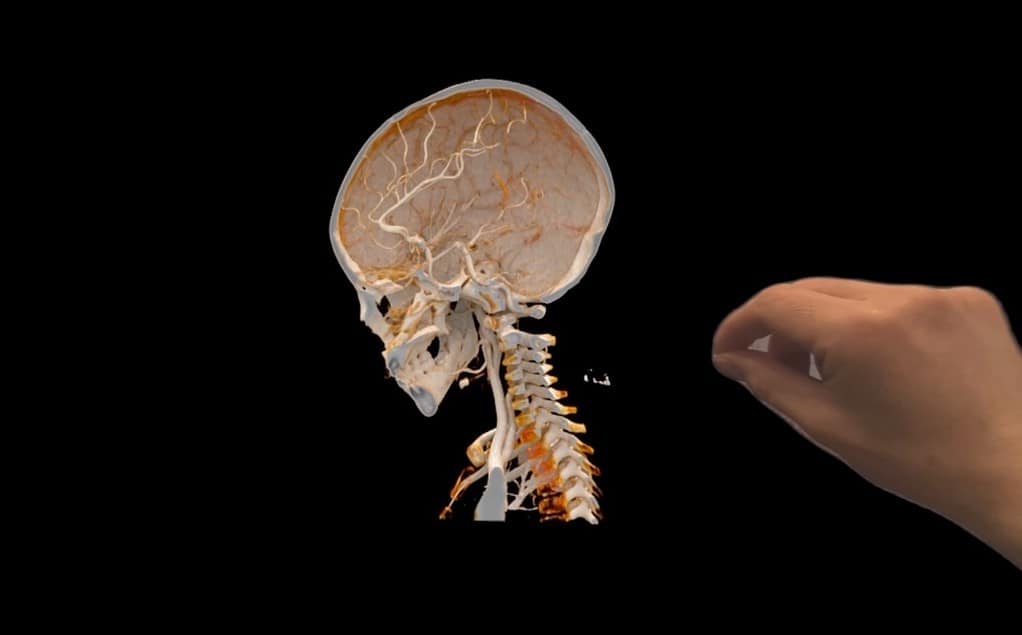

3. Interactive Holograms of The Human Body

With the Cinematic Reality app, Apple allows surgeons, medical students, and patients to witness dynamic, immersive holographic representations of the human body in their actual environment thanks to Apple Vision Pro.

To make this work, Apple says this application combines path-tracing technology with Metal and the M2 processor’s capabilities to simulate light interactions with virtual objects and produce realistic lighting and reflections.